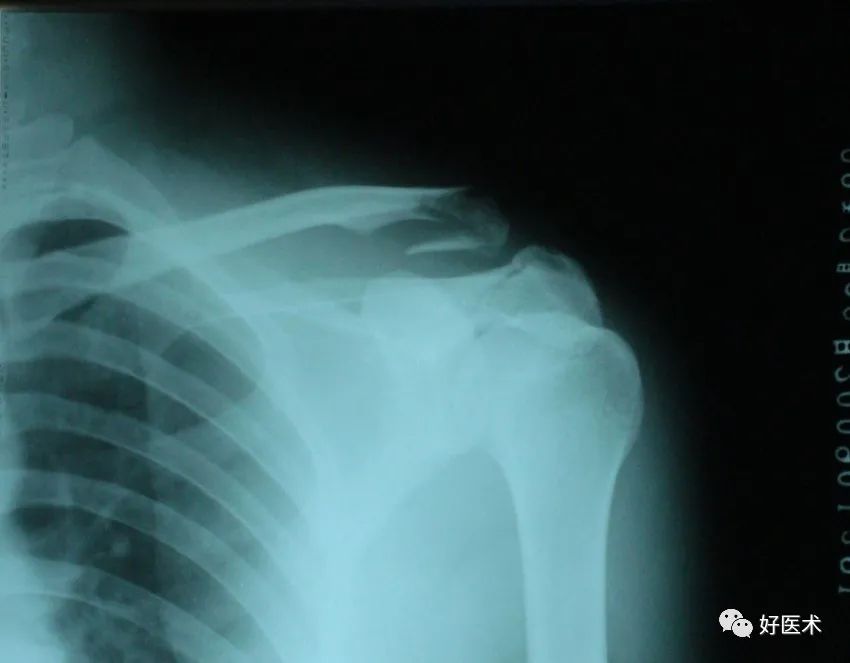

推荐 四肢骨折后石膏外固定详解 好医术早读文章 好医术 赋能医生守护生命